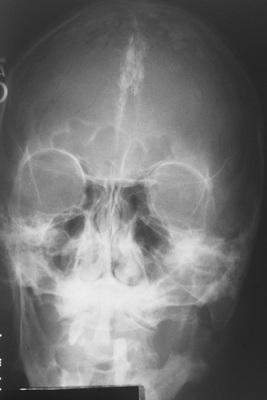

Anteroposterior skull film showing calcification of the falx cerebri.

nevoid basal cell carcinoma syndrome

Large cysts present in the right and left mandibular molar regions, together with a smaller cyst involving the right maxillary canine.